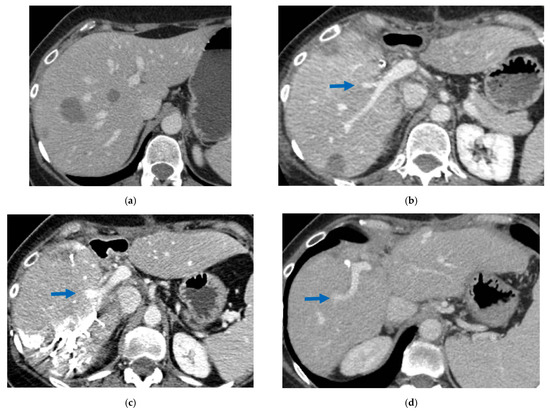

3.3. PS-TSH with SS-PVE

Super-selective portal vein embolization was performed in three patients since the resection of first-order GPs was deemed not necessary and a TWO-STAGE major PSH with SS-PVE was planned. Percutaneous PVE was achieved under US guidance via an ipsilateral approach through the tumor-bearing liver in two patients and via a contralateral approach through the future remnant liver in one patient. The accesses were respectively by S6, S5 and S3 portal vein branches under US guidance and local anesthesia. In all three cases S1/S4 were anatomically resected en-bloc with MHV at the first stage (MLP). Super-selective PVE consisted in embolization of portal branch for S6/S7/S8 in one case, for S7/S8 in one case and for S5/S8 in one case. The second stage was performed 58, 57 and 63 days after the first stage and consisted in the resection of S6/S7/S8 with RHV skeletonization in one case (see Figure 6 and Figure 7), in resection of S7/S8 partially extended to S5/S6 en-bloc with RHV reconstructed with an end-to-end anastomosis in one case (see Figure 8) and in resection of S7/S8/S5 en-bloc with RHV reconstructed with end-to-end anastomosis in another case. No complications occurred after surgery and patients were discharged from the hospital on the 11th, 11th and 17th post-operative day. The primary was resected at the time of the first stage (right hemicolectomy) in two cases and before the first stage (left hemicolectomy, “primary first” strategy) in one case.

Figure 6. CT Images of PS-TSH with SS-PVE performed to treat 35 bilateral CRLMs. (a) Partial response after FOLFOXIRI + Bevacizumab 12 cycles; FLR (=S2/S3) volume is 15%. (b) Blue arrow points GP 5 after the first stage consisting of resection of S1/S4 extended to S2/S8/S5 plus metastasectomy of S2 with tangential resection of LHV. (c) Fourteen days after stage 1 SS-PVE was performed on the right liver preserving GP 5 (blue arrow); 37 days after SS-PVE FLR (=S2/S3/S5) increased up to 37%. (d) Blue arrow points GP 5. Twenty-five months after PS-TSH with SS-PVE the patient is disease free; the liver’s only disease recurrence was successfully treated with another 3 liver resections (2 on the right liver and 1 on the left). Abbreviations: PS-TSH: parenchyma-sparing TWO-STAGE hepatectomy; SS-PVE: super-selective portal vein embolization; CRLM: colorectal liver metastases; FLR: future liver remnant; S: segment; GP5: glissonean pedicle for segment 5; LHV: left hepatic vein.